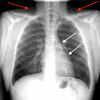

A Case of Spontaneous Pneumomediastinum Following Ecstasy and Marijuana Use

Spontaneous pneumomediastinum (SPM) is a benign and self-limiting condition more commonly seen in young adults. Radiology imaging of the chest, including X-ray or CT scan, is the gold standard for diagnosis. Ecstasy, also known as 3,4-methylenedioxymethamphetamine (MDMA) is a synthetic amphetamine derivative widely abused for an increased sense of well-being and euphoria. Marijuana is also abused for recreational purposes. SPM has been reported after both Ecstasy and marijuana use. SPM after these illicit drugs abuse usually has a benign and self-limiting course with supportive management. However, it is always important to rule out serious associated conditions like esophageal perforation. Here, we present a 22-year-old male who developed SPM after Ecstasy ingestion and marijuana inhalation.